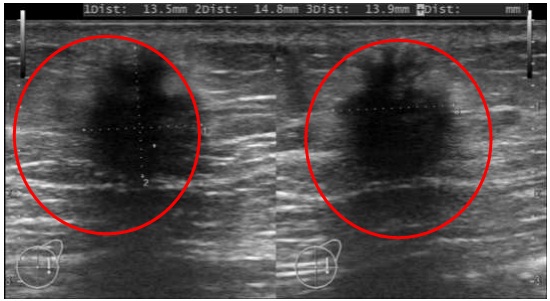

- Siêu âm tuyến vú: Nốt giảm âm vú phải BIRADS 4C

Hình 1. Siêu âm tuyến vú: Nốt giảm âm vú phải vị trí 12h, cách núm vú 5cm, kích thước 13,5×14,8×13,9mm, bờ thuỳ múi lớn, trục lớn vuông góc với mặt da ( vòng tròn màu đỏ)